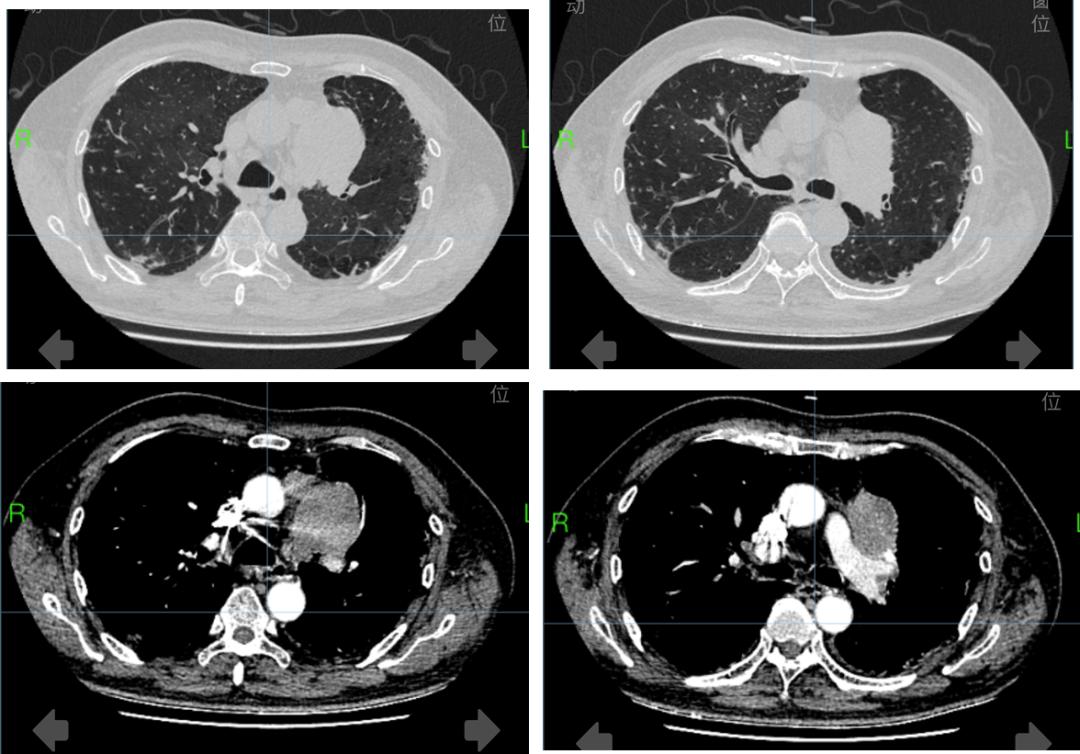

入院查体显示,患者全身皮肤粘膜无黄染,颜面部紫红色皮疹,颈部、左腕部大片红斑,伴有双手指间关节、掌指关节出皮疹,伴有色素沉着,脱屑,皮肤粗糙,双侧大腿外侧可见暗红色皮疹。颈部、腹股沟、腋下可及肿大的淋巴结(图1)。心电图显示该患者存在窦性心律及频发房性早搏,胸部CT显示左肺上叶尖后段胸膜下团块影,纵膈内多发软组织团块影级结节影(图2)。颅脑CT显示双侧基底节区及双侧半卵圆中心腔隙灶,考虑横纹肌溶解。予以对症处理效果欠佳,患者仍有全身发酸乏力伴皮肤大面积红疹需进一步诊治,故拟「 皮疹待查:皮肌炎? 」收治入院。

图2

•肺恶性肿瘤伴纵膈、肺门淋巴结转移:患者老年男性,有吸烟史。胸部CT增强扫描+三维重建显示,左肺上叶胸膜下、左上纵隔及肺门旁肿块,考虑恶性,伴纵隔淋巴结肿大,左侧胸腔少量积液。左肺上叶尖后段胸膜下团块影,较既往逐年增大。肿瘤指标中糖类抗原125、NSE升高,结合影像学表现, 考虑肺恶性肿瘤伴纵膈淋巴结转移可能 ,需进一步支气管镜、肺穿刺活检等明确病理。

•淋巴瘤:患者胸部CT增强扫描+三维重建显示,左肺上叶胸膜下、左上纵隔及肺门旁肿块,考虑恶性,伴纵隔淋巴结肿大,左侧胸腔少量积液;患者有明显双上肢水肿、颜面部水肿,考虑有淋巴道阻塞表现, 需考虑淋巴瘤可能 ,需待经皮肺肿块穿刺活检明确病理。